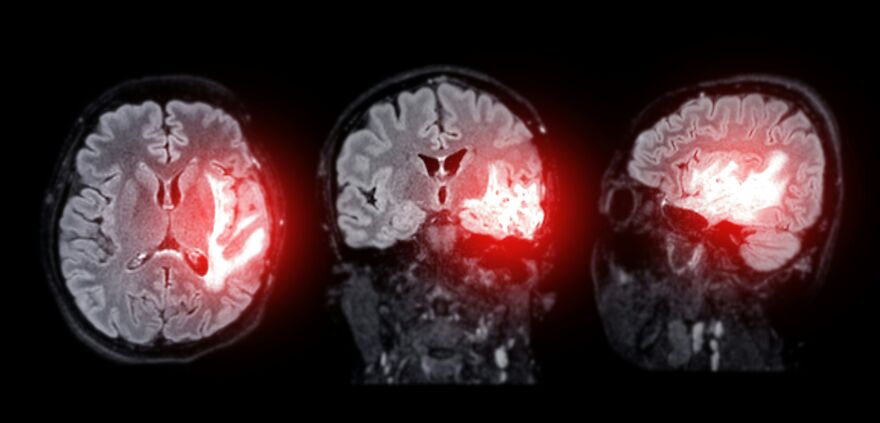

“In rare cases the sudden spike in pressure can rupture blood vessels in the brain leading to subarachnoid hemorrhage,” which is a life-threatening condition where blood seeps between the brain and its protective membranes.

Image credits: Unsplash / Tomasz Gawłowski

He goes on to say that this risk is higher in individuals prone to aneurysms and weakened arteries.